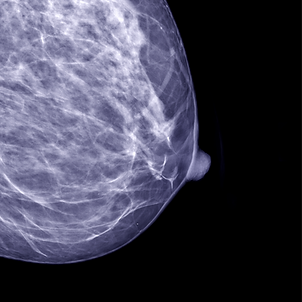

La mammographie est un examen réalisé par une technologue spécialisée en imagerie mammaire. Cette technique, couramment utilisée dans le cadre du dépistage du cancer du sein (PQDCS) ou à des fins diagnostiques, utilise des rayons X pour obtenir des images détaillées des tissus mammaires. Elle permet la détection de lésions bénignes ou malignes avant même l’apparition de symptômes.

Le sein est formé de glandes qui se superposent, de vaisseaux sanguins et de tissus adipeux. Bien qu'elle puisse être inconfortable, la compression élimine le flou lié aux mouvements, permet d'utiliser une dose plus faible de radiation et est essentielle pour faciliter la détection des anomalies en dispersant la glande et les autres structures internes du sein.

La tomosynthèse est une technique d'imagerie médicale qui permet l'obtention d'images reconstruites en trois dimensions des tissus mammaires. Par sa précision, cette technique diminue le nombre d'examens complémentaires et favorise une meilleure détection des lésions comparativement à la mammographie conventionnelle.